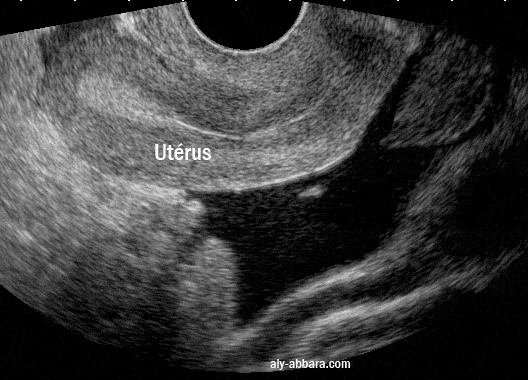

Image montrant l'aspect échographique d'un hémopéritoine suite à une rupture d'un kyste fonctionnel ovarien

• Il s'agit d'un épanchement du sang lysé et de caillots occupant la totalité du cul-de-sac postérieur (de Douglas)